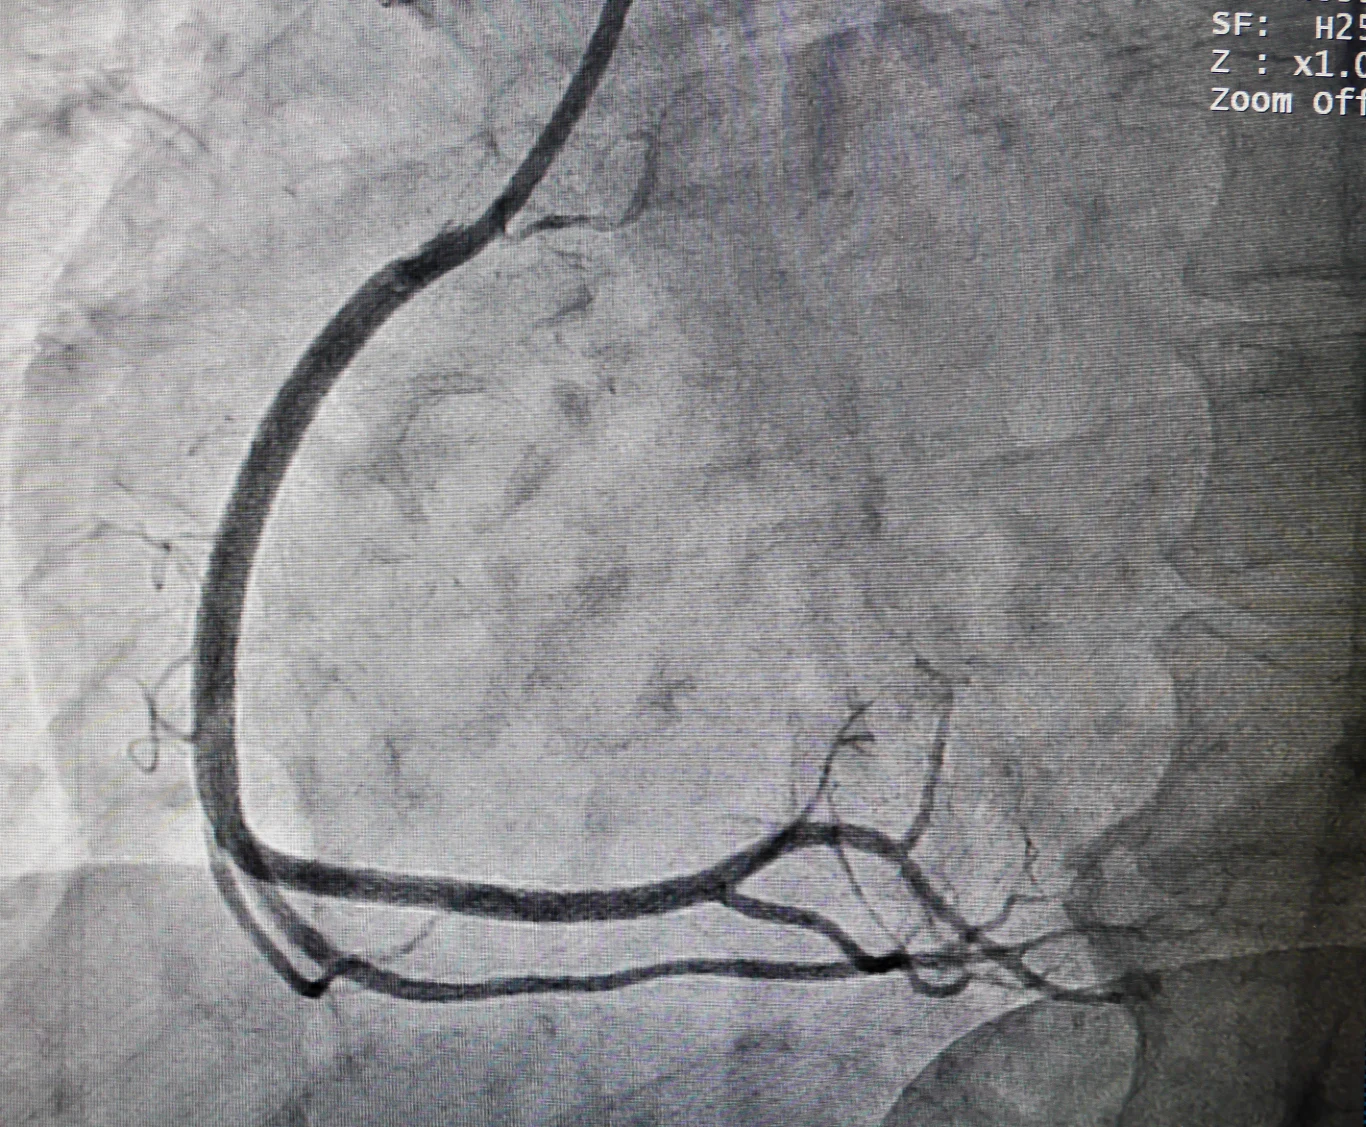

Poprzez zlokalizowanie w tętnicach ewentualnych przewężeń, koronarografia pozwala ocenić stopień zaawansowania zmian miażdżycowych oraz ocenić skuteczność leczenia.

Jeżeli tętnice są zwężone, może to wywołać niedokrwienie serca, czyli chorobę wieńcową. Jeżeli zaś któraś z tętnic wieńcowych ulega zatkaniu, konsekwencją jest zawał serca. Nic więc dziwnego, że koronarografię zaleca się u pacjentów z podejrzeniem choroby niedokrwiennej serca.

Badanie to pozwoli na rozpoznanie, która tętnica została zamknięta, dzięki czemu można w porę udrożnić zablokowane naczynie i rozszerzyć zwężenie. W efekcie prostym wnioskiem jest fakt, że koronarografia ratuje życie.